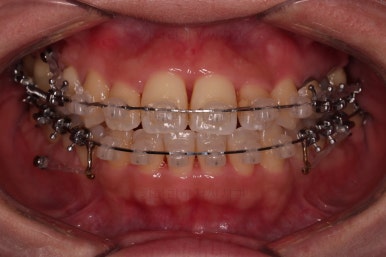

장치를 부착한 모습 참고해 주시고요.

아랫니는 중앙선을 맞추기 위해서 미니스크류를 이용해 한 쪽으로 당기는 중이고요.

이 과정에서 아랫니들이 약간은 뒤로 들어가져서 아랫입술 부위의 돌출감을 아주 약간은 줄일 수 있습니다.

윗니 임플란트 할 자리는 적절히 계속 맞춰줍니다.

중앙선도 점점 맞아지고 있어요.

임플란트 할 공간도 여유롭게 마련이 되었네요.